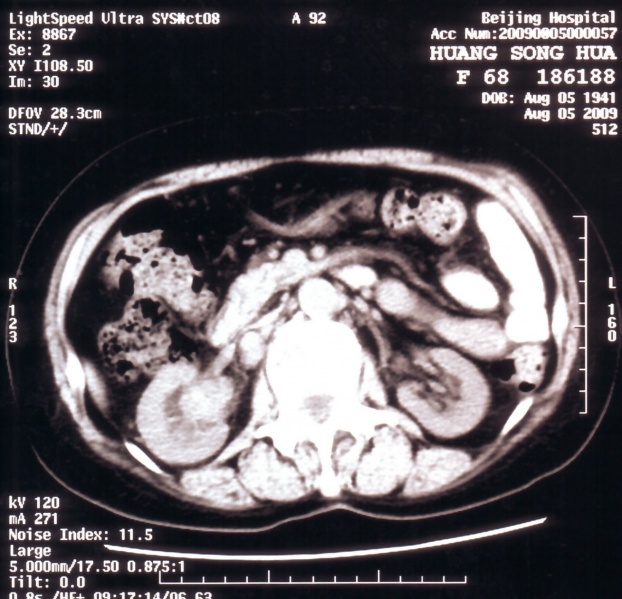

肾癌